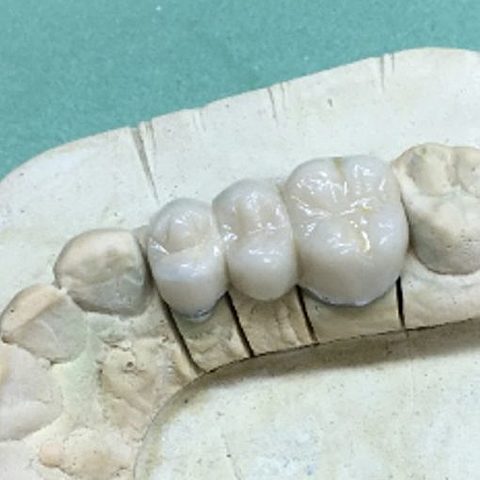

• Prueba bizcocho.

Prueba bizcocho.

Prueba de bizcocho de las coronas.

• Entrega coronas e impresión para prótesis removible.

Entrega coronas e impresión para prótesis removible.

Cementado de coronas e impresión para la elaboración de prótesis removible.